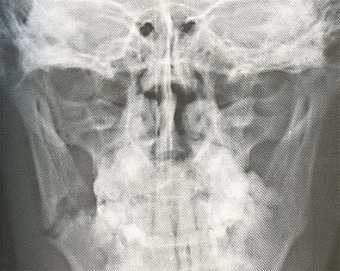

С данной травмой обращаются к врачу — отоларингологу. Врач осмотрит пациента, оценит степень травмы, соберет анамнез. При пальпации носовой области определит болезненный участок, наличие воздуха, крепитацию фрагментов кости и подвижность наружного носа. Также специалист выявит вид деформации носовой пирамиды и степень отека мягких тканей. Очень важно обратить внимание на наличие у пострадавшего кровотечения и головной боли, потери сознания, рвоты или тошноты. Обязательно проводят инструментальные исследования — рентген и риноскопию.

Рентгенографическое исследование поможет определить вид травмы (открытый, закрытый, со смещение или без) и локализацию повреждения (иногда это можно определит путем пальпации). Риноскопия выявляет степень отека слизистой оболочки, вероятное искривление перегородки, место разрыва слизистой и первоисточник носовой геморрагии. Важно определить наличие сопутствующих недугов и носовых повреждений в прошлом.

Рентгенографическое исследование черепа. Снимки, полученные в ходе обследования, позволяют врачу увидеть места перелома и количество, а также смещение отломков. Помимо травмы органа дыхания, с помощью рентгенографического исследования выявляются возможные повреждения черепных костей.

Рентген носа позволяет не только определить локализацию отломков и состояние костей травмированного органа, но и сопутствующие повреждения черепа. На рентгеновском снимке четко видны разрывы костной ткани и все линии перелома. Рентгенография осуществляется в двух проекциях для более полного поминания травмы.